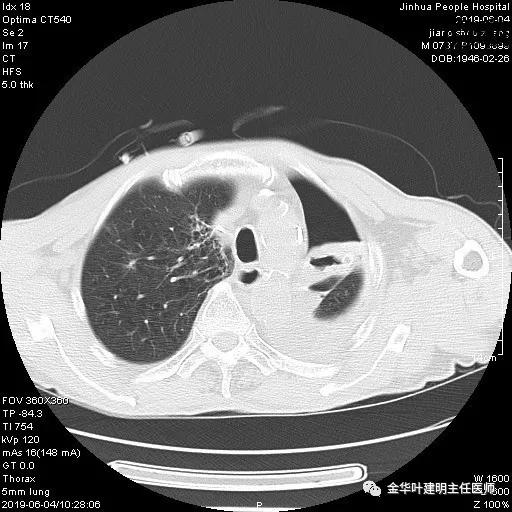

6.4上午:24小时引流出血性乳糜液1800毫升。是否再次手术进行右进胸胸导管结扎,抑或继续保守治疗非常纠结!压力非常大!!多方讨论会诊无法取得一致意见,但一般认为,引流量在1000毫升以上宜积极手术。情况与浙二医院范军强教授联系,请求指导,范教授认为左侧肺手术,损伤胸导管主干的机会较小,多数可保守治疗而愈。在他们的病例中,也有结扎胸导管后引流量仍无减少,效果并不能完全保证。建议可以考虑胸管夹管观察(因为淋巴管压力低,予以适当的压力,漏出量可能会明显减少),同时继续禁食,并静脉营养支持,引流管口可能会有渗液,注意更换敷料。与家属充分沟通后决定试夹管;这天血色素9.0 g/L;胸部CT复查示: